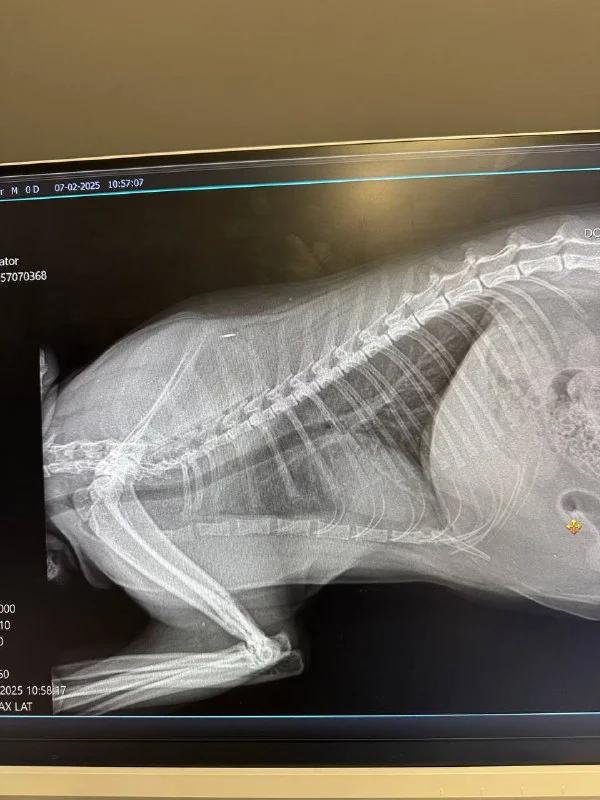

У нашего кота периодически бывают приступы, отдалённо похожие на кашель. Мы записали их на видео и показали доктору Мариосу в Animal Health. На приёме сделали рентген и взяли анализ крови – оба результата были в норме. Доктор сказал, что это похоже на астму или аллергию, и посоветовал попробовать давать Prednicortone 5 mg в течение нескольких дней. Если поможет – значит, скорее всего, астма.

Хорошо бы диагноз сначала поставить, вообще симптомы астмы можно увидеть на ренгене 😰

Имеет. В Лимассоле не посоветую, в Ларнаке попробуйте обсудить дополнительную диагностику(бронхоальвеолярный лаваж, исключить лёгочных паразитов, NT‑proBNP) с Натальей в Zookosmos. В данный момент у вас нет диагноза так как вариантов пяток точно наберется. Вариант с таблетками без точного диагноза - плохой.

Врача кстати зовут Маринос, а не Мариос, если вы были в Animal Health. Он хирург, как хороший диагност замечен не был :)

Расскажу. Нам тоже в ближайшей ветке прописали таблетки сначала, но, посоветовавшись с другими вет, решили перейти на ингалляции. Мне посоветовали съездить в V3ts к доктору Кириякосу. Он сказал, что на 90% уверен, что астма, но если позволяет бюджет, стоит сделать лаваж. Это делается под наркозом и стоит 600€.(Рентген тоже вроде бы сделали). Мы сделали, никаких бактерий не было найдено- но зато теперь мы знаем, что это точно астма. Прописал 2 препарата, помогает. Делаем обычным детским спейсером из аптеки, тк надеемся выйти в ремиссию.

Вот анализы крови и видео, как это выглядит

Рентген еще нашла